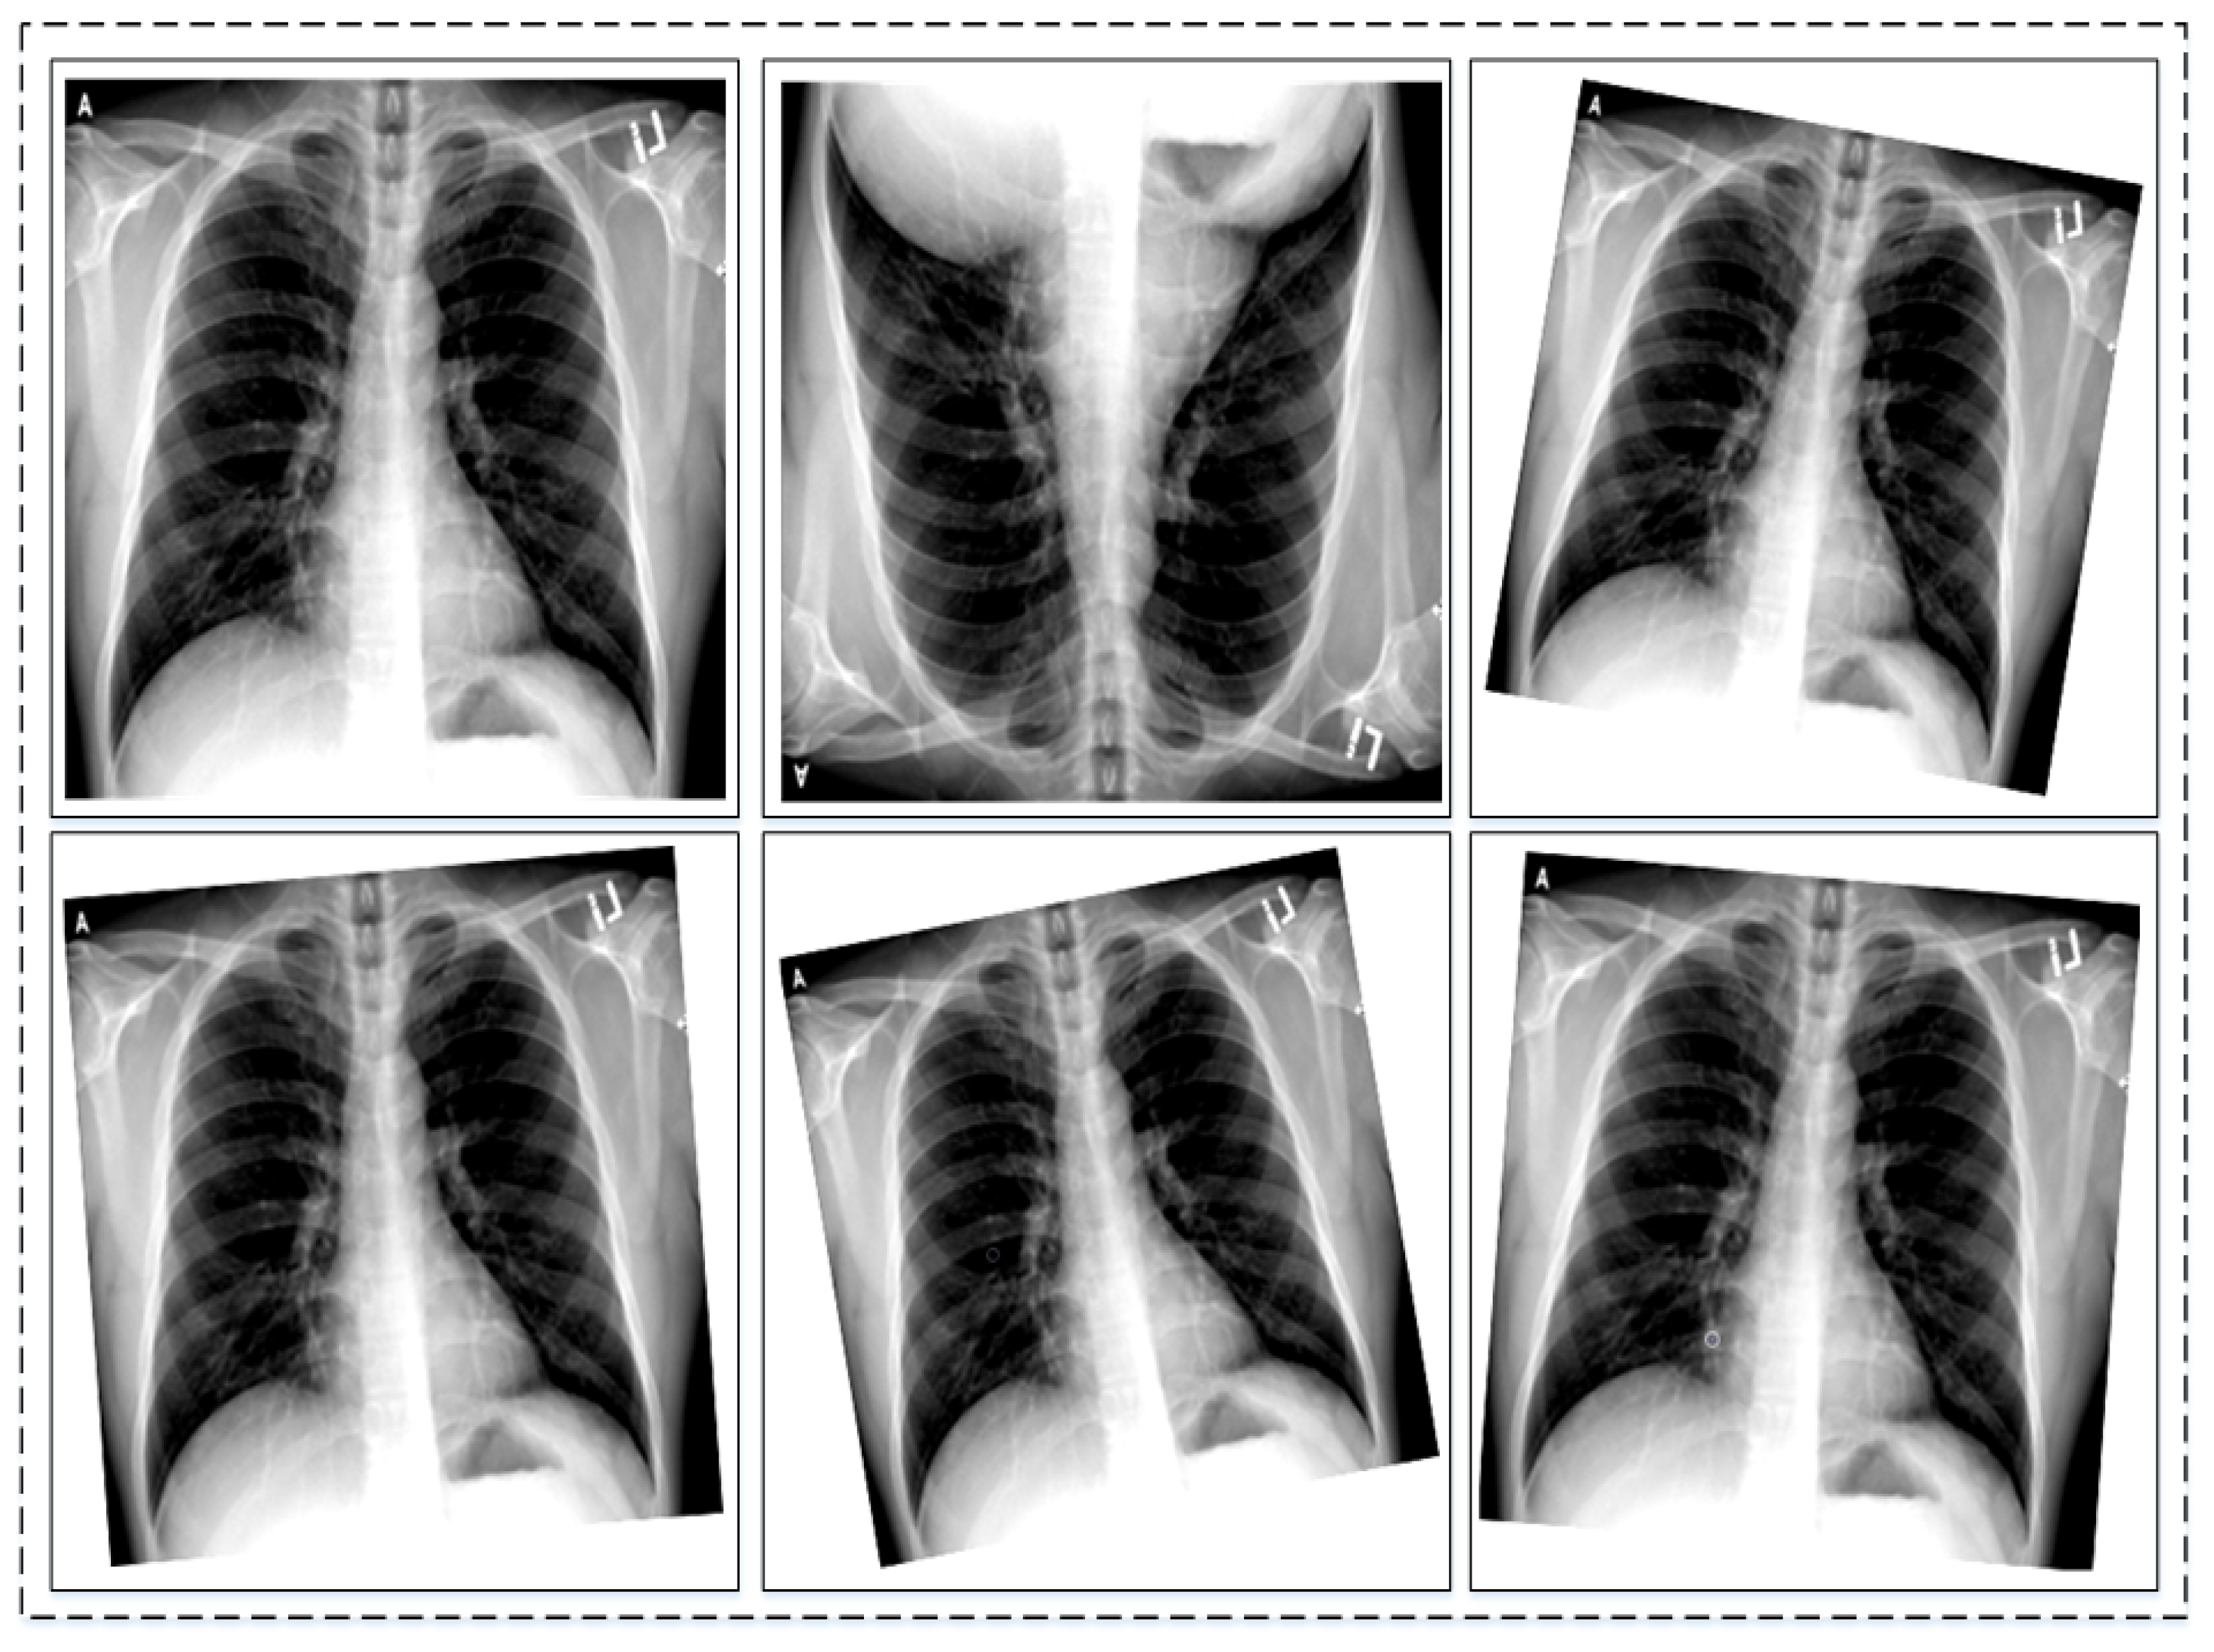

3.1. Dataset